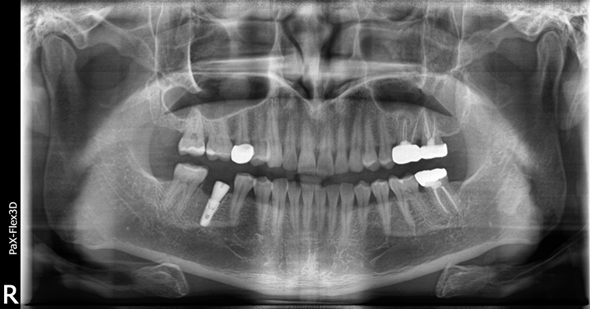

(전, 후) 2022년 2월 5일

소개해드릴 환자분은 작년 봄에 저희 디데이치과에 내원하셔서 검진 후 치료를 받으셨던 분인데요.

이 때, 기존에 이미 크라운을 씌워둔 오른쪽 아래 어금니의 상태가 좋지 않아서 경과를 지켜봐야 할 것 같다고 말씀을 드렸습니다.

그런데 결국 이 치아가 말썽이 생겨 내원해주셨습니다.

검진 결과 해당 치아에 염증이 생겨 발치 후 임플란트 해야한다고 말씀을 드렸고, 염증이 있기는 했지만 다행히 심하지 않아서

내원해주신 당일 오른쪽 아래 어금니 임플란트 식립을 진행할 수 있었습니다.

보시면 당일에 바로 치아 발치 후 임플란트 식립까지 완료된 모습을 확인하실 수 있습니다 ^^

치아 머리 부분에 해당하는 보철물은 임플란트의 금속 픽스처가 뼈와 충분하게 유착되어 단단해질 때까지 기다렸다가

약 3개월 후인 지난 4월 말에 최종적으로 부착해 마무리 해드렸습니다.

환자분은 내원 당일 임플란트 식립이 가능했고, 뼈가 튼튼한 케이스라 임플란트가 잘 고정되어

내원 횟수를 최소화하고 치료 기간도 약 3개월 정도로 마무리할 수 있었습니다 ^^